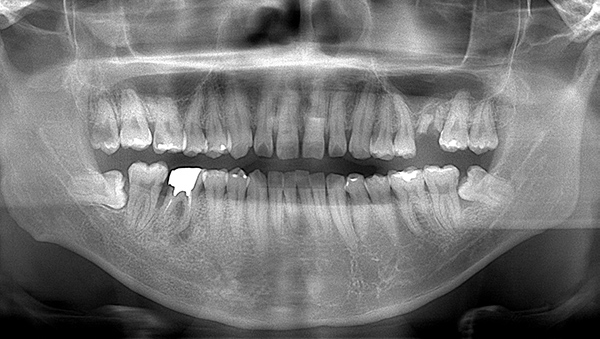

パノラマレントゲン写真

説明:

上顎左側臼歯部に残根があり周囲に透過像が見られる。また下顎右側臼歯部に根尖部から根分岐部に及ぶ透過像がある。また左右上下顎智歯には歯髄に達する透過像や歯冠周囲を覆う透過像が見られ歯周疾患が進行していることが取れる。

臼歯部に残根状態の歯牙があり、またカリエス(虫歯)の散在が認められる。残根部分の両隣在歯は欠損部に対して傾斜し始めている。

下顎右側臼歯部には一見大きな問題はないように見えるが、 頰側にフィステルと言われる排膿路があり発赤と主張があり炎症状態が続いていた。

前歯部には離開部位があり、歯頚部にはカリエスが認められる。

年齢・性別 30代・男性

主訴 奥歯が痛くて噛めない

治療期間 半年間

治療費 合計:1,595,000円 (内訳)

・左上567ジルコニアブリッジ: 110,000×3本

・右下567ジルコニアブリッジ: 110,000×3本

・右上6ジルコニアクラウン:110,000×1本

・左下6、右上45セラミックインレー:55,000×3本

・上顎前歯部: 165,000×4本

治療方針 ・保存不可能な歯の抜歯

・歯周病治療

・根管治療(歯の根っこの治療)

・虫歯治療

・審美治療

治療内容 ・抜歯:右下第1大臼歯はCT撮影後歯根破折を認めた。また左上第一大臼歯は残根(根っこだけ残っている)状態だっため両方共抜歯の適応となり処置を行った。また上下左右親知らずも大きな虫歯になっており、歯周病を惹起しており抜歯となった。

・歯周病治療:全体的に歯肉の炎症が強く、歯磨き指導と刺繍基本治療を行い消炎処置をまず行った。その後、歯周ポケット(歯と歯茎の溝)の深部にある歯石の除去を行った。

・根管治療:右上第1大臼歯は虫歯が大きく神経に達していたため、根管治療を行い被せ物を行う。

・虫歯治療:その他虫歯のある部位はセラミックにて治療。

・審美治療:矯正治療を行う時間がないため、被せ物にて治療を行う。Waxupにてシュミレーションを行い、治療の際はあまり歯を削らないように行う。

治療のリスク・副作用 歯ぎしり・食いしばりが強い方は、セラミックが割れてしまうことがあります。半年に一度の定期検診でかみ合わせや歯周病や虫歯のチェックが必要です。